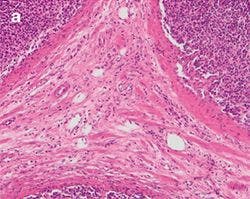

The practical effect of the color shift caused by a generic LED light source, both with and without a CC filter, is clearly visible when imaging a stained tissue section using the different light sources. Figure 5 shows a tissue section illuminated by the three different light sources mentioned before.

Figure 5: Stained Tissue Section b

Figure 5: Stained Tissue Section

Differences between halogen lamp (a) and LED illumination (b) lead to tissue stainings shifting to blue, both through the oculars and on the screen. Adding a CC filter (c) mitigates the issue, but still gives a yellowish appearance.